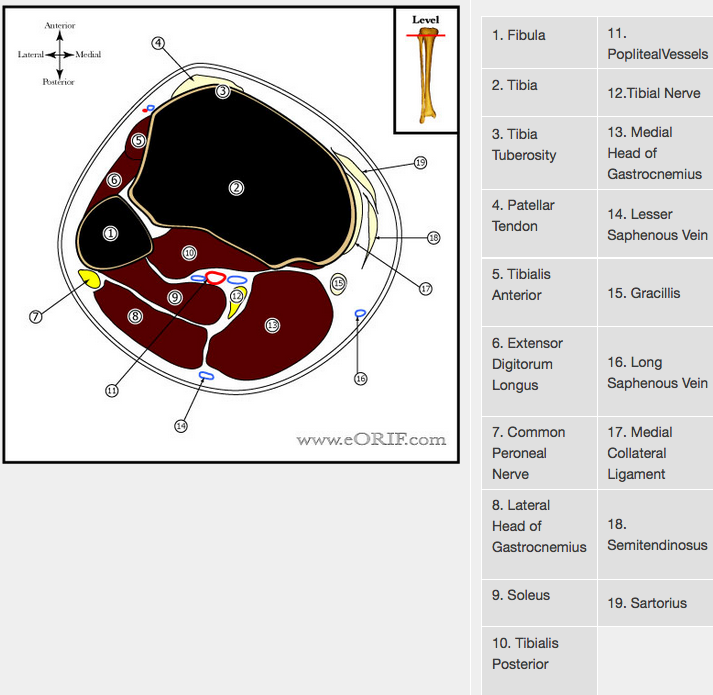

NAME THE ANATOMICAL STRUCTURES

Name the structures

name the structures

- Cephalic vein

- FCR

- FDS

- ulnar artery

- ulnar nerve

- FCU

- FDP

- basilic vein

- ulnar shaft

- APL

- PIN

- ECU

- EDM

- Supinator

- FPL

- Radial shaft

- deep branch of radial nerve

- EDC

- ECRB

- ECRL

- BR

- Superficial radial nerve

- PT

- radial artery

- median nerve

- volar (flexors)

- Dorsal (extensors)

- mobile wad